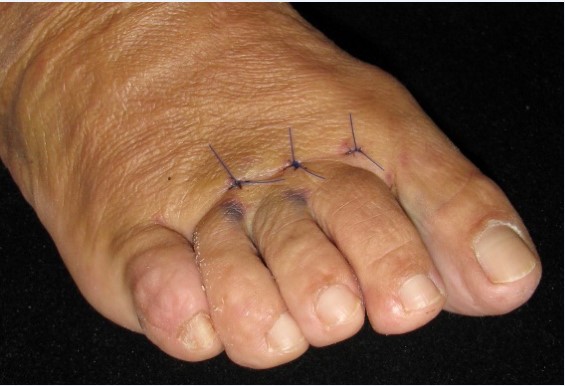

Para la corrección del hallux valgus se realizaron osteotomías abiertas, diafisaria tipo scarf o en chevron distal, con forma de “V”, y la osteotomía percutánea distal de M1 tipo Reverdin-Isham. En muchos casos se completó con una osteotomía de Akin [7] de la base de la primera falange del primer dedo del pie (Figura 4).

Figura 4a

Figura 4b

Figura 4c

Figura 4. Evolución radiográfica de metatarsalgia asociada a hallux valgas tratada con técnica de Reverdin-Isham, radiografía dorso – plantar a) preoperatoria, b) postoperatoria, c) al año de la intervención